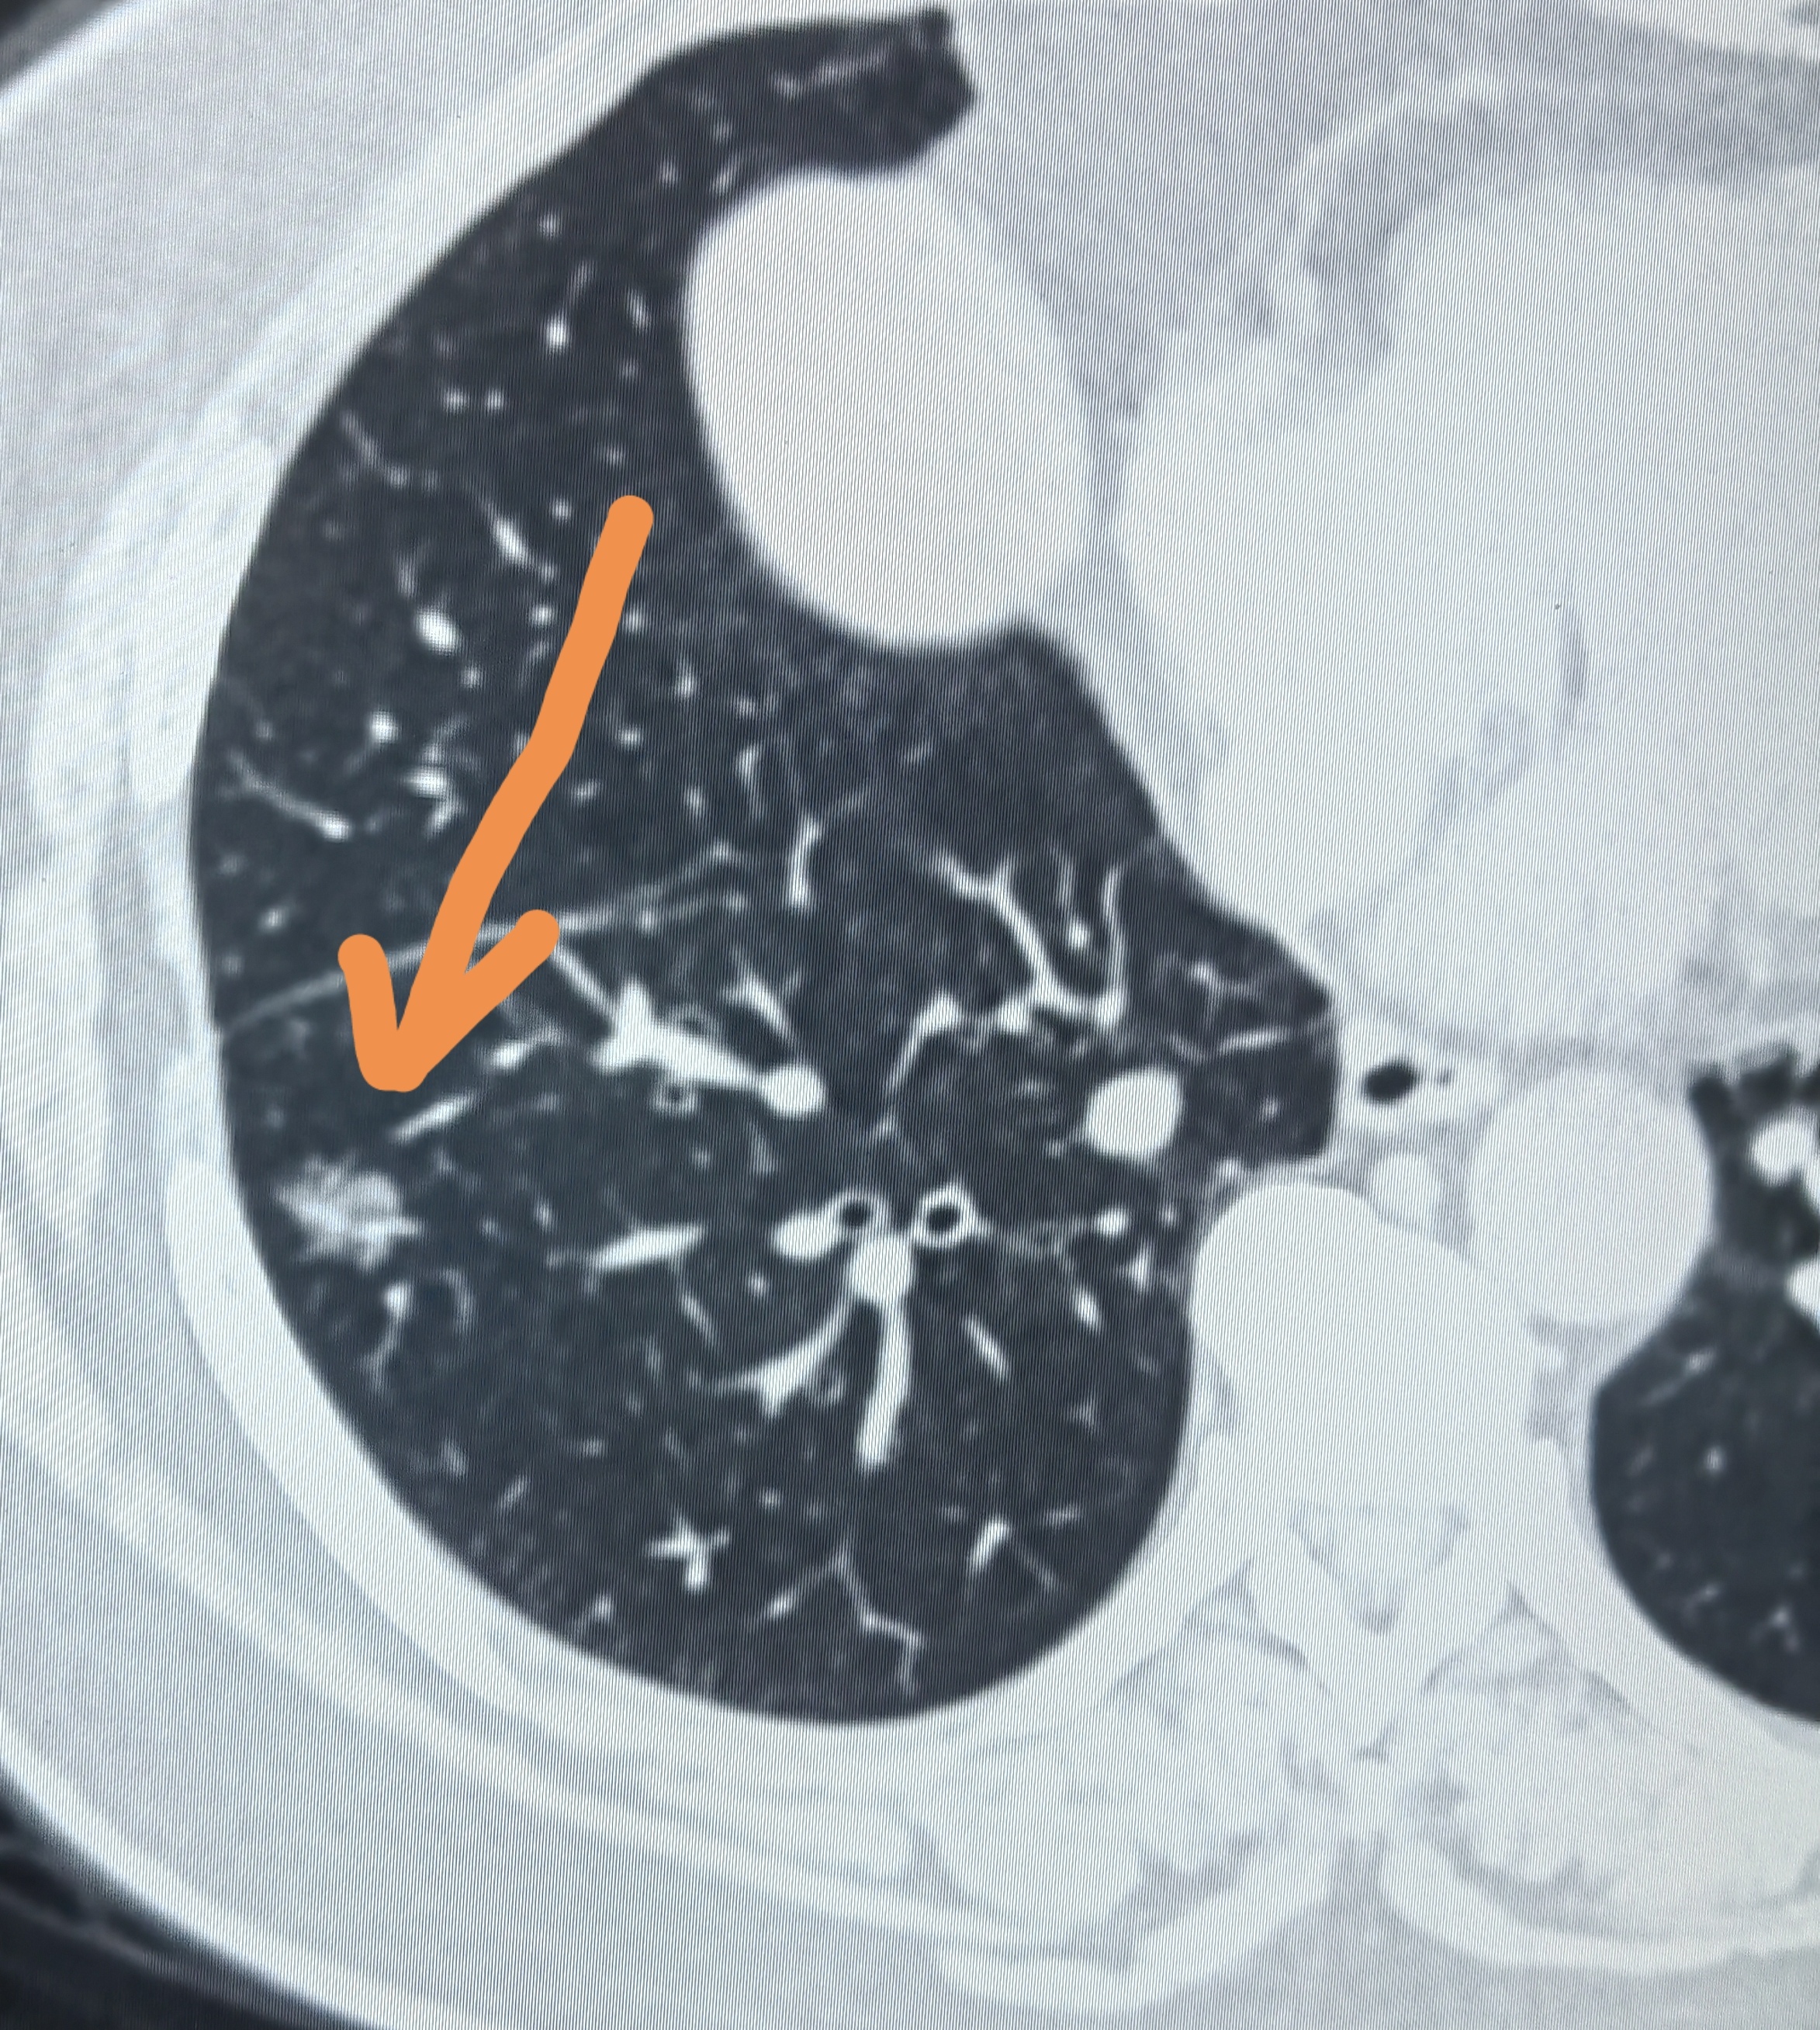

肺結(jié)節(jié)是指肺部CT檢查影像上直徑≤3cm的邊緣清楚或模糊的局灶性圓形密度增高灶。多見于20~40歲成年人,女性略多于男性。根據(jù)其密度表現(xiàn),將其分為實(shí)性結(jié)節(jié)和非實(shí)性結(jié)節(jié)(即磨玻璃結(jié)節(jié),或稱部分實(shí)性結(jié)節(jié)、亞實(shí)性結(jié)節(jié))。一般認(rèn)為肺結(jié)節(jié)直徑<8mm者在短時(shí)間內(nèi)發(fā)展為惡性腫瘤的可能性相對較小或腫瘤倍增時(shí)間相對較長,目前對這類肺結(jié)節(jié)的性質(zhì)較難準(zhǔn)確判斷,一般都是定期隨診復(fù)查,根據(jù)其動態(tài)變化情況來判斷是性質(zhì)。

磨玻璃結(jié)節(jié)不都是肺癌,只是其中的一部分會是肺癌。磨玻璃結(jié)節(jié)分類:根據(jù)其密度表現(xiàn)分為:純磨玻璃結(jié)節(jié)和混合磨玻璃結(jié)節(jié);根據(jù)其性質(zhì)分為:良性磨玻璃結(jié)節(jié)和惡性磨玻璃結(jié)節(jié)。良性磨玻璃結(jié)節(jié)常見于局灶性肺炎、間質(zhì)性炎癥、纖維化、小血管畸形、出血、不典型腺瘤樣增生(現(xiàn)在還包括原位癌)等;惡磨玻璃結(jié)節(jié)有肺微浸潤腺癌、浸潤性腺癌。當(dāng)然磨玻璃結(jié)節(jié)也可分為腫瘤性結(jié)節(jié)和非腫瘤性結(jié)節(jié)。表現(xiàn)為磨玻璃結(jié)節(jié)的肺癌只是磨玻璃結(jié)節(jié)中的一小部分,多數(shù)磨玻璃結(jié)節(jié)是良性的。良、惡性磨玻璃結(jié)節(jié)的表現(xiàn)形態(tài)、生長規(guī)律是不一樣的,如何鑒別磨玻璃結(jié)節(jié)的良、惡性就得由專業(yè)醫(yī)師來做了。